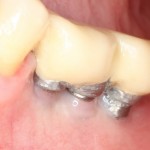

Хотите посмотреть, как на самом деле выглядит протез, изготовленный за 3 дня, и установленный на базальные импланты? Смотрите:

На протезе вы видите следы многочисленных коррекций и ремонтов. Зубы на нижнем и верхнем протезе в боковых участках из-за постоянных подточек, практически потеряли форму, не функциональны. И я объясню вам, почему такое происходит.

Дело в том, что со временем, по мере утраты зубов, у пациента перестраивается весь жевательный аппарат: изменения происходят в челюстных суставах, жевательных мышцах, челюстных костях и т. д. Тотальное протезирование на имплантах — весьма сложная штука, ведь врачу-ортопеду и зубного технику требуется определить такое соотношение челюстей, какое было тогда, когда у пациента еще были все зубы на месте. Это очень сложный, деликатный и важный этап диагностики. Умные доктора это знают, именно поэтому даже при небольшом протезировании используют различные виды функциональной диагностики. Здесь же ничего подобного не было. Работу максимально упростили — ну да, завышают протезы? Подточим! Не смыкаются? Наплавим! А то, что при этом чувствует пациент, что у него происходит с челюстными суставами и жевательными мышцами, как мне кажется, никто не задумывается.